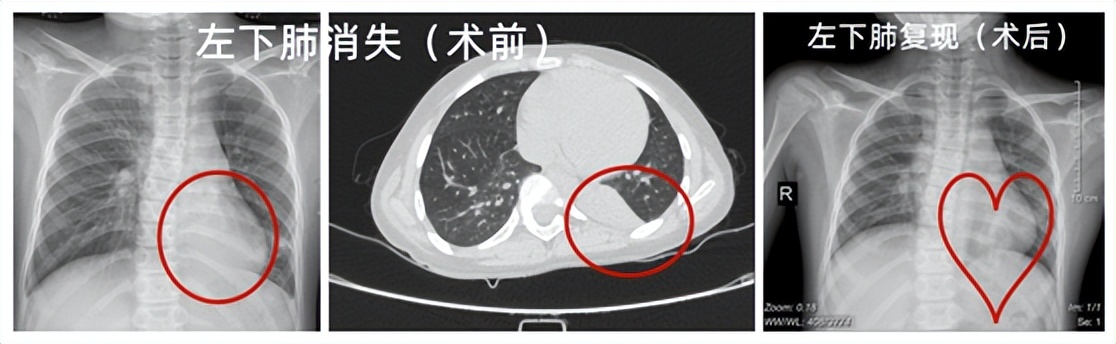

支气管镜术前/后影像对比图

患儿,9岁,女,因“咳嗽20余天伴喘息3天”收住儿童呼吸科,入院前在多家医院就诊,诊断“支气管肺炎”,经治疗后病情反复,入院后查胸部CT示左下叶支气管狭窄伴左肺下叶不张。余刚副主任医师于2022年7月29日行支气管镜检查发现左肺下叶基底段可见一淡黄色痰栓,予异物钳、冷冻等处理,取出较多痰栓,仍有部分残留。遂于2022年8月5日再次行支气管镜术,经儿童呼吸介入团队不懈努力,成功取出了患儿肺里的支气管塑形。术后第二天患儿症状缓解,复查胸片提示左下肺复张,予出院。